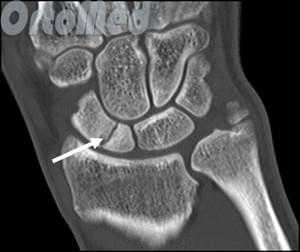

Всем пациентам перед операцией осуществляли рентгенографию кистевого сустава в трех проекциях (прямая, боковая, полупронация) и компьютерную томографию.

Функция пальцев полная. Сила кулачного схвата правой (доминантной) кисти — 22 кг, снижена почти в 2 раза по сравнению с нормой. Сила схвата левой кисти — 40 кг. Оценка по шкале ВАШ — 3 балла, по опроснику DASH — 21,16 балла. На рентгенограмме (рис. 5, а, б, в) и при компьютерной томографии выявлен ложный сустав ладьевидной кости (см. рис. 6, г). Рис. 6. Пациент К., 19 лет. Диагноз: ложный сустав ладьевидной кости правой кисти. а — рентгенограмма в прямой проекции; б — рентгенограмма в ¾; в — рентгенограмма в боковой проекции; г — компьютерная томография.

В некоторых случаях, когда по рентгенограмме тяжело определить соотношение отломков назначается компьютерная томография лучезапястного сустава. При таком исследовании можно трехмерно увидеть поврежденную кость, что поможет в определении тактики оперативного лечения перелома.

Начинать диагностику лучше всего с осмотра у врача, при подозрении на травму запястья делают рентгенограммы лучезапястного сустава. Важно сделать помимо стандартных прямой и боковой проекций еще и дополнительную косую, в которой лучше всего будет видна ладьевидная кость. Бывает так, что на первичных рентгенограммах перелом не выявляется. При сохранении симптоматики и отсутствии признаков костной травмы на рентгене следует повторить исследование через неделю или сделать компьютерную томографию (КТ) для уверенного подтверждения или исключения перелома.

Компьютерная томография (КТ). Это весьма информативный метод диагностики переломов, позволяющий более точно оценить в т.ч. характер смещения фрагментов ладьевидной кости. Информация, полученная при КТ, поможет доктору выбрать наиболее оптимальную тактику лечения.